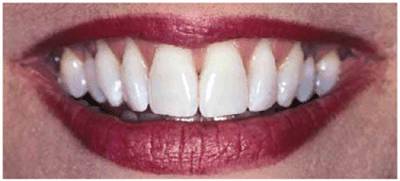

Some examples of these different discolorations can be seen in Figures 16-2A

and B 16-8A and B 16-11A and B 16-12A and B, and ,. Additionally, the discoloration

can either be of a generalized nature or specific to one tooth or one location

on a tooth (Table 16-2).

Figure 16-2A and B: Total neglect resulted in severe staining

of this patient's teeth.